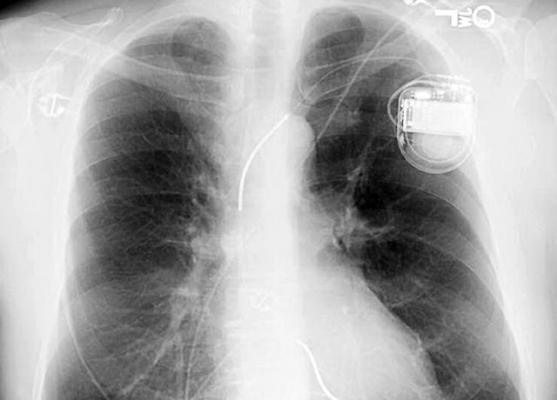

To use the neural network, the clinician uploads the X-ray image containing the device into a computer and the software reads the image to give a result on the make and model of the device within seconds.

The team used the program to see if it could identify the devices from radiographic images of more than 1,500 patients at Hammersmith Hospital between 1998 and 2018. They then compared the results with five cardiologists who used the current flowchart algorithm to identify the devices.